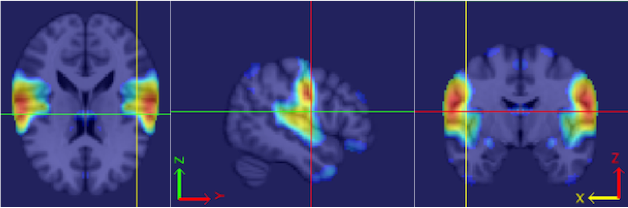

Our procedure is as follows. Each fMRI scan was separated into left and right hemispheres. Thus, each hemisphere contained voxels. Similar to standard group ICA (Calhoun et al., 2001b), a dimension reduction using PCA was applied to each hemisphere of each subject. 15 PCs are obtained for each hemisphere. A group data matrix was generated by concatenating the reduced data of both hemispheres of the 20 subjects in the temporal domain. Thus, the aggregated matrix has dimension , where , , and . Our algorithm of homotopic group ICA is then applied on this matrix. Fifteen estimated independent components are postulated by H-gICA. As shown in Figure 12, out of the 15 components, several brain networks were found including: the visual network 12, the default mode network 12, the auditory network 12, and the motor network 12. Compared with the ICs obtained from ordinary gICA, shown in 12, 12, 12 and 12, H-gICA improves the estimation of all of these sources by yielding substantially more clearly delineated networks.